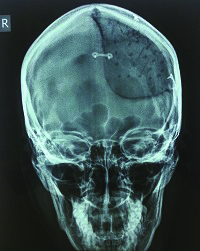

A 23-year-old woman presented at the University Hospital Osijek, Croatia, department of neurosurgery, with a benign change in the bones of her skull. The deformed part of the skull was on her forehead, and highly visible. In addition to needing to remove part of the diseased bone, doctors determined that it was also necessary to address the woman’s cosmetic defects in order to reduce the psychological consequences of the surgery.

Traditionally, this procedure, a cranioplasty, required surgeons to tailor polymethyl-methacrylate (PMMA) bone cement implants to the patient’s skull using silicone molds. But these molds often have poor aesthetic results, long production times and high costs. Additionally, the operation would be lengthy and the final outcome was not guaranteed.

Before 3D printing, the surgeon had to shape the bone cement implant by hand. The aesthetic results were poor, the operation lasted longer and the outcome was less sure. With 3D printing, the outcome is much better because the implant is tailored to an individual’s CT scan.

A 23-year old woman’s successful cranioplasty using 3D printing technology.